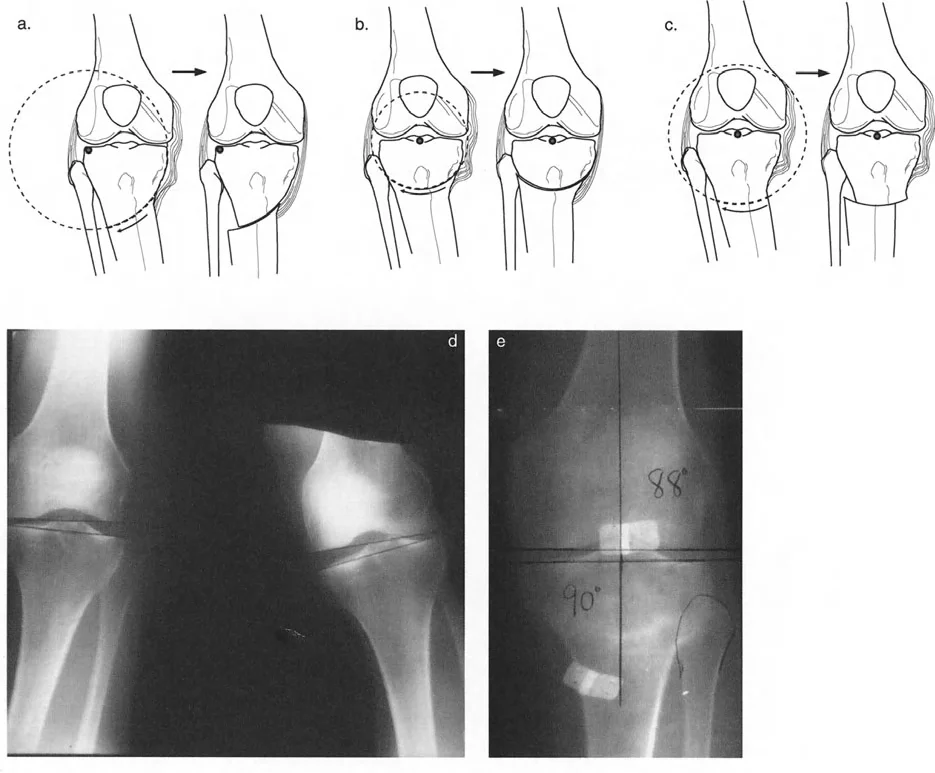

مبادئ جراحة إعادة المحاذاة

تتمثل الفكرة الأساسية في تغيير زاوية عظم الساق (الظنبوب) أو عظم الفخذ (أحيانًا)، لإعادة توزيع الحمل على مفصل الركبة.

- في حالات التقوس (Varus deformity): حيث يكون الحمل زائدًا على الحجرة الإنسية (الداخلية)، يتم إجراء قطع العظم لتحويل الساق إلى وضعية الروح (Valgus)، مما ينقل الحمل إلى الحجرة الوحشية (الخارجية) السليمة.

- تخفيف الحمل: في الركبة الطبيعية، تتحمل الحجرة الإنسية حوالي 75% من الحمل أثناء الوقوف على ساق واحدة. مع 6 درجات فقط من التقوس الميكانيكي، يمكن أن يصل الحمل إلى 95%. تهدف الجراحة إلى تقليل هذا الحمل إلى حوالي 50% أو أقل.

تحديد هدف التصحيح (نقطة فوجيساوا)

- نقطة فوجيساوا (Fujisawa Point): أوصى فوجيساوا وزملاؤه (1979) بأن يمر المحور الميكانيكي للطرف السفلي بين 30% و 40% وحشيًا لمركز أشواك الظنبوب لتحقيق أفضل النتائج. يُطلق على هذه المسافة "نقطة فوجيساوا".

- تعديلات جاكوب وميرفي (Jakob and Murphy 1992): تم تعديل توصية فوجيساوا بناءً على مقدار الغضروف المتبقي في الحجرة الإنسية.

- إذا كانت مسافة المفصل طبيعية: هدف التصحيح هو MAD (الانحراف المحوري الميكانيكي) = 0.

- إذا كان هناك فقدان لثلث الغضروف: هدف التصحيح هو ثلث نقطة فوجيساوا.

- إذا كان هناك فقدان لثلثي الغضروف: هدف التصحيح هو ثلثي نقطة فوجيساوا.

- إذا كان هناك فقدان كامل للغضروف (عظم على عظم): هدف التصحيح هو نقطة فوجيساوا كاملة.